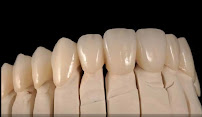

• Fixed and Removable Prosthetics — crowns, bridges, partial and full dentures, and implant-retained prostheses